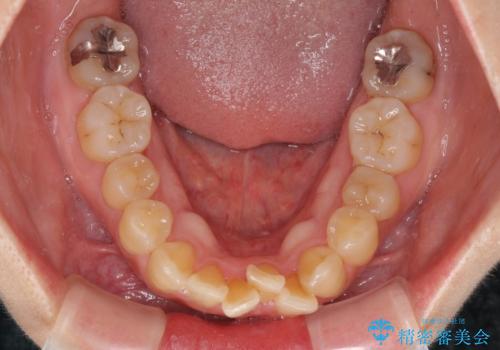

舌の突出癖により治療期間中に開咬となり、治療が長引きましたが、口元も治療前よりも引っ込めることができ、すっきりとした仕上がりとなりました。

抜歯矯正により口元を引っ込めることも検討しましたが、特に口元の突出感は気になっていないとのことで、非抜歯にてワイヤー装置で矯正治療を行うこととしました。